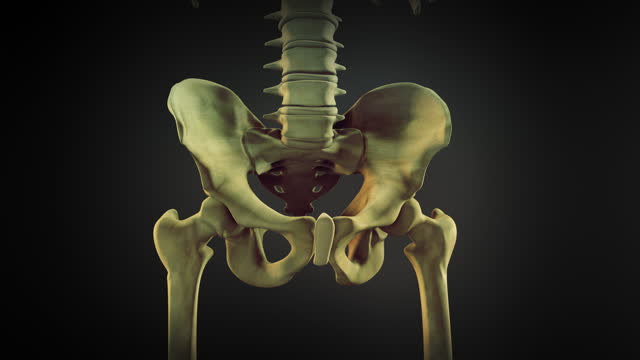

고관절 수술 후 회복에 필요한 시간을 알려드려요. 고관절 수술은 고관절의 변화로 인한 통증 및 기능 장애를 개선하기 위해 수술적인 처리를 하고, 수술 후 환자들은 회복 기간을 거치게 됩니다.

고관절 수술후 회복기간- 수술 후 1주일: 치료와 통증 관리

수술 후 1주일은 가장 중요한 시기입니다. 이 때에는 처음 수술에 대한 통증이 가장 심하며, 치료와 통증 관리에 집중해야 합니다. 수술 부위를 올바르게 관리하고, 의사의 지시에 따라 정확히 약물을 복용하는 것이 중요합니다. 또한, 특별한 동작을 하지 않도록 주의해야 합니다. 1주일 동안은 휠체어를 사용하거나 보조기를 사용하는 것이 좋습니다.